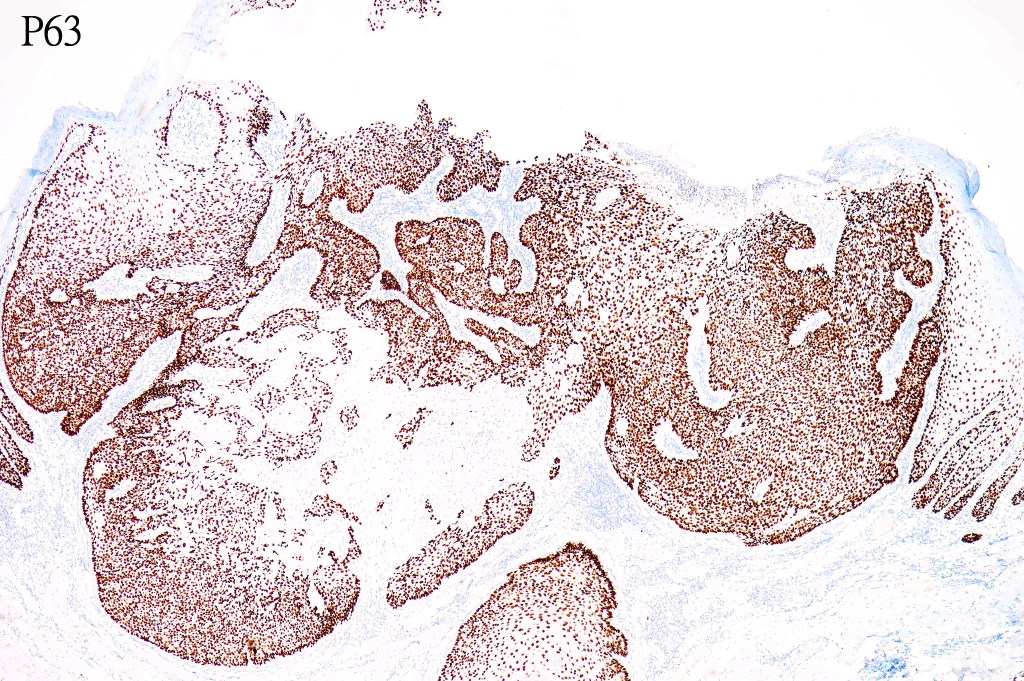

•CD34, p63 +ve